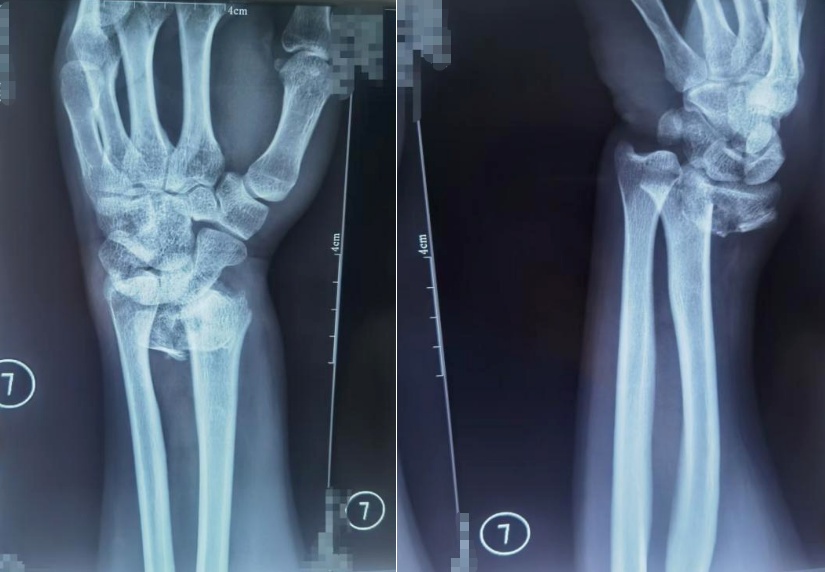

示意图:一位患者桡骨远端骨折,图为复位前正位、复位前侧位。图源:哈尔滨骨伤科医院微信公众号

据介绍,11时至17时30分,积水潭医院新街口院区急诊科共接诊滑倒摔伤患者40人,其中骨折患者超20人,一大半都是桡骨远端骨折。“大多数人滑倒后的第一反应是手撑地,摔倒时受的力经手腕传导至前臂,从而形成桡骨远端骨折。”接诊医生介绍,桡骨骨折患者往往会感到腕部及前臂肿胀、疼痛,严重骨折时局部还会发生畸形,如有相关症状要及时就医。